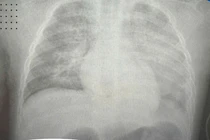

Bệnh viện Việt Nam – Thụy Điển Uông Bí vừa tiếp nhận trường hợp nam thanh niên 17 tuổi (Hoàng Quế - Đông Triều) nhập viện trong tình trạng viêm da tiếp xúc bội nhiễm nghiêm trọng sau khi tự điều trị bệnh tại nhà.

Tuy nhiên tình trạng bệnh không đỡ, các ban phát triển nhiều, xuất hiện các nốt phỏng nước toàn thân, nhiều mảng trượt da, bong vảy. Lúc này gia đình mới đưa người bệnh đến Bệnh viện Việt Nam – Thụy Điển Uông Bí.

Tại bệnh viện, các bác sĩ chẩn đoán người bệnh bị viêm da tiếp xúc bội nhiễm. Người bệnh đang được điều trị kháng sinh kết hợp chăm sóc da tổn thương. Hiện sức khỏe người bệnh ổn định và đã được xuất viện.